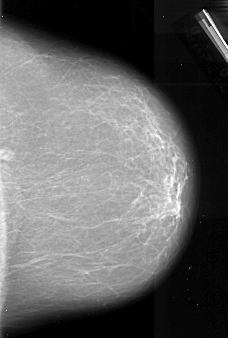

A_1011_1.LEFT_CC

LEFT_CC LINES 6346 PIXELS_PER_LINE 4381 BITS_PER_PIXEL 16 RESOLUTION 42 OVERLAY